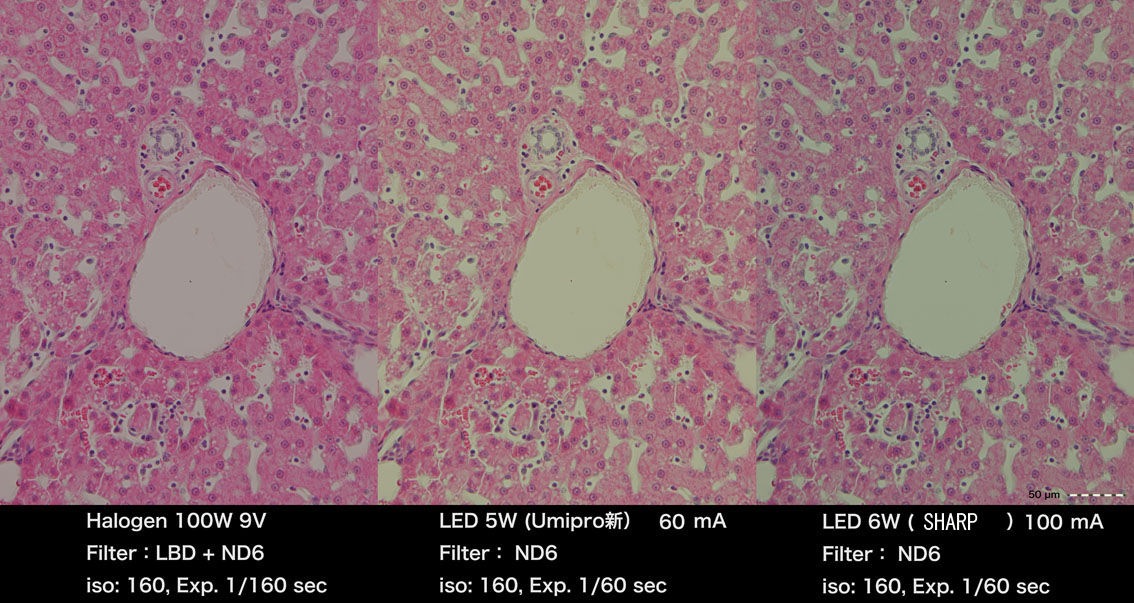

ハロゲン、演色度98新5WLED、従来型シャープ6Wを標本で比較したものです。

琉球大学、泉水様より提供していただきました。